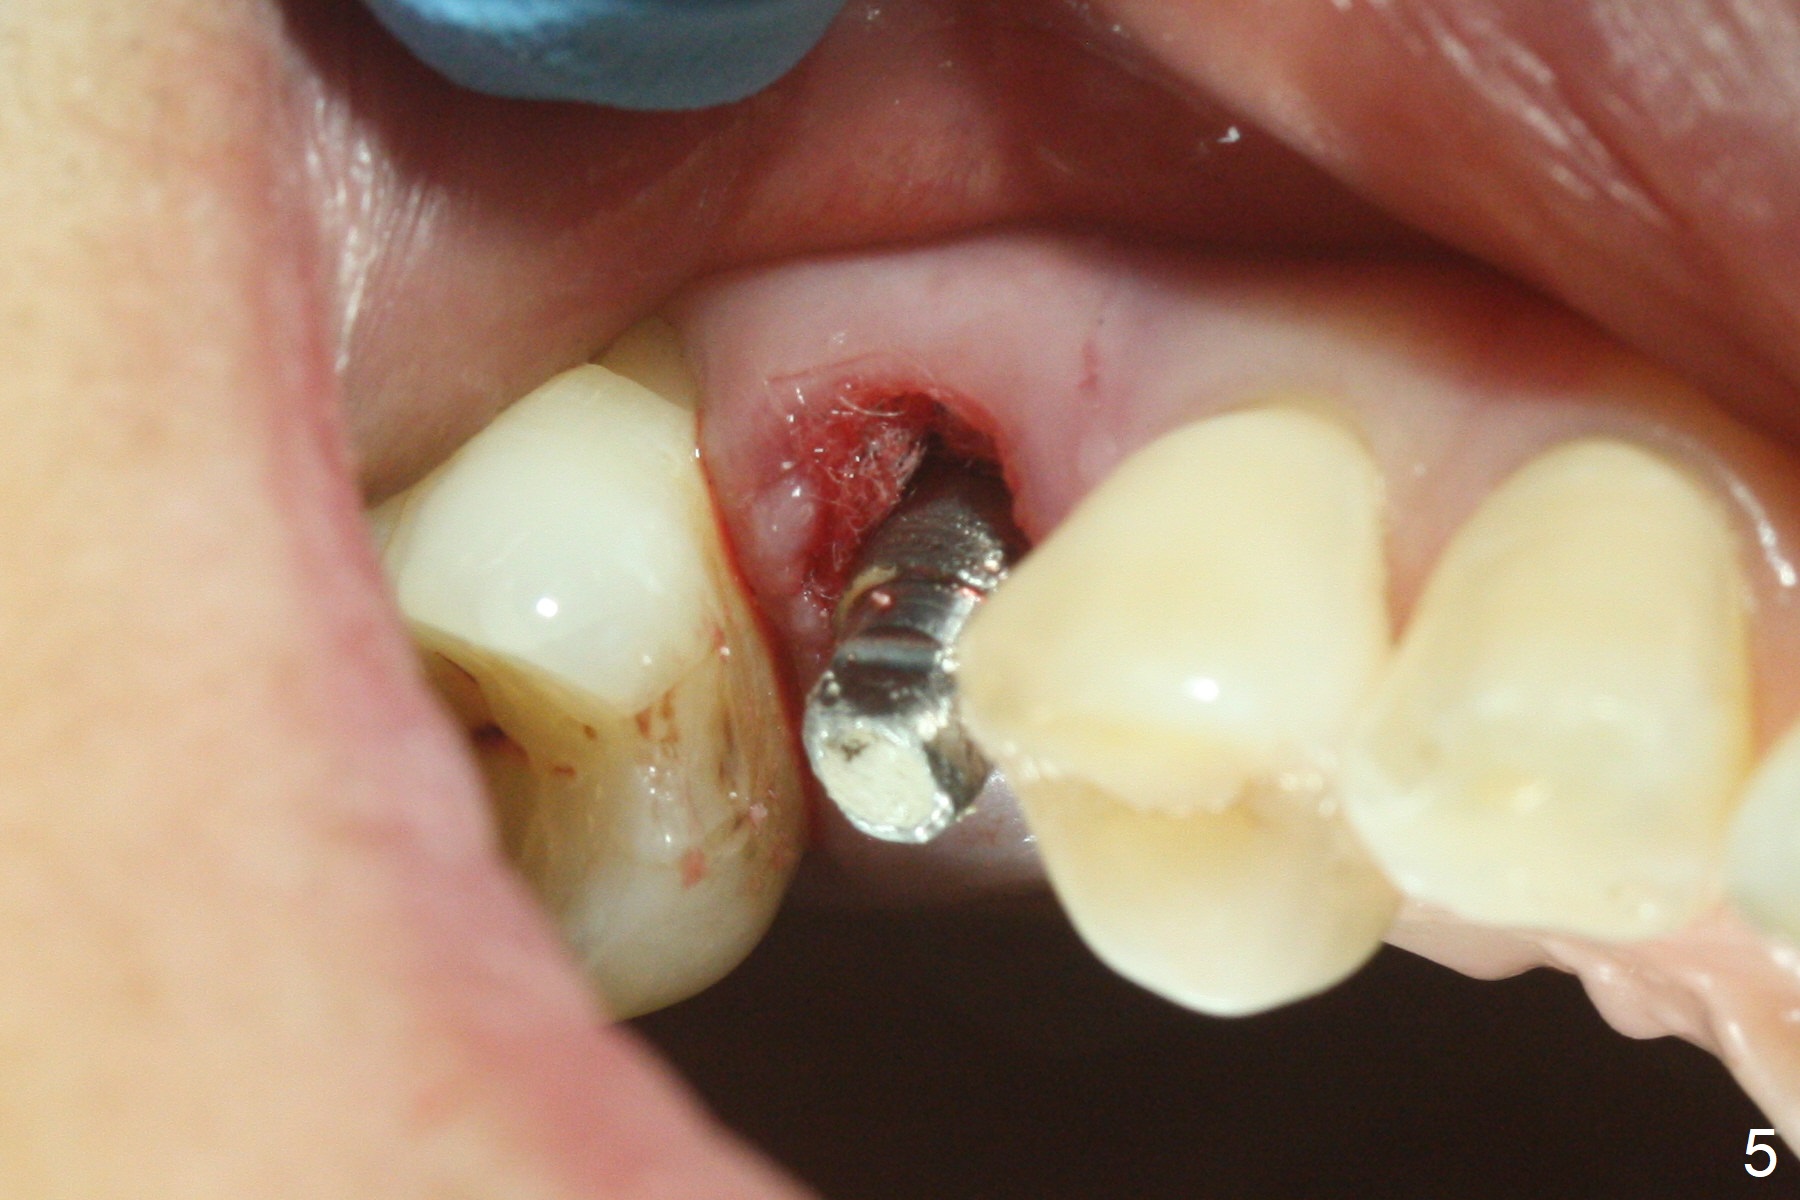

After extraction of residual root at #4 with mesiopalatal subgingival margin (Fig.1), the mesiopalatal crestal bone loss is noted. Instead of the mesial slope, the initial point of the osteotomy is at the mesial and middle (buccopalatally) of the socket bottom (Fig.2, 2'). The initial depth with 2 mm drill is 20 mm (gingival level), while the last drill (3 mm) is used for 17 mm (because of soft bone). When a 3.8x16 mm implant is placed (Fig.3,4), the distal gap of the socket is closed, suggesting that the implant moves to the least resistant area. However, it is favorable to the mesial crestal defect (Fig.4). The buccopalatal position of the abutment (4.5x4(4) mm) is a little too palatal (Fig.5, taken prior to provisional fabrication). The implant seems to have osteointegrated 6 months postop (Fig.6).